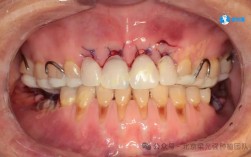

适用于轻度牙性偏颌,主要问题源于牙齿排列不齐、中线偏离、牙弓不对称等,骨骼结构基本正常,通过牙齿移动可纠正咬合关系,改善面部对称性,常用矫治器包括:

- 传统托槽矫治:通过金属或陶瓷托槽施加精准矫治力,适用于复杂病例,可灵活调整牙齿位置和咬合关系;

- 隐形矫治:利用透明牙套逐步移动牙齿,美观舒适,适合对美观要求高的患者,但需严格佩戴(每天20-22小时),且对严重偏颌的调整能力有限;

- 舌侧矫治:将托槽粘贴于牙齿舌侧,完全隐形,技术难度高、费用昂贵,适合对美观要求极致的患者。